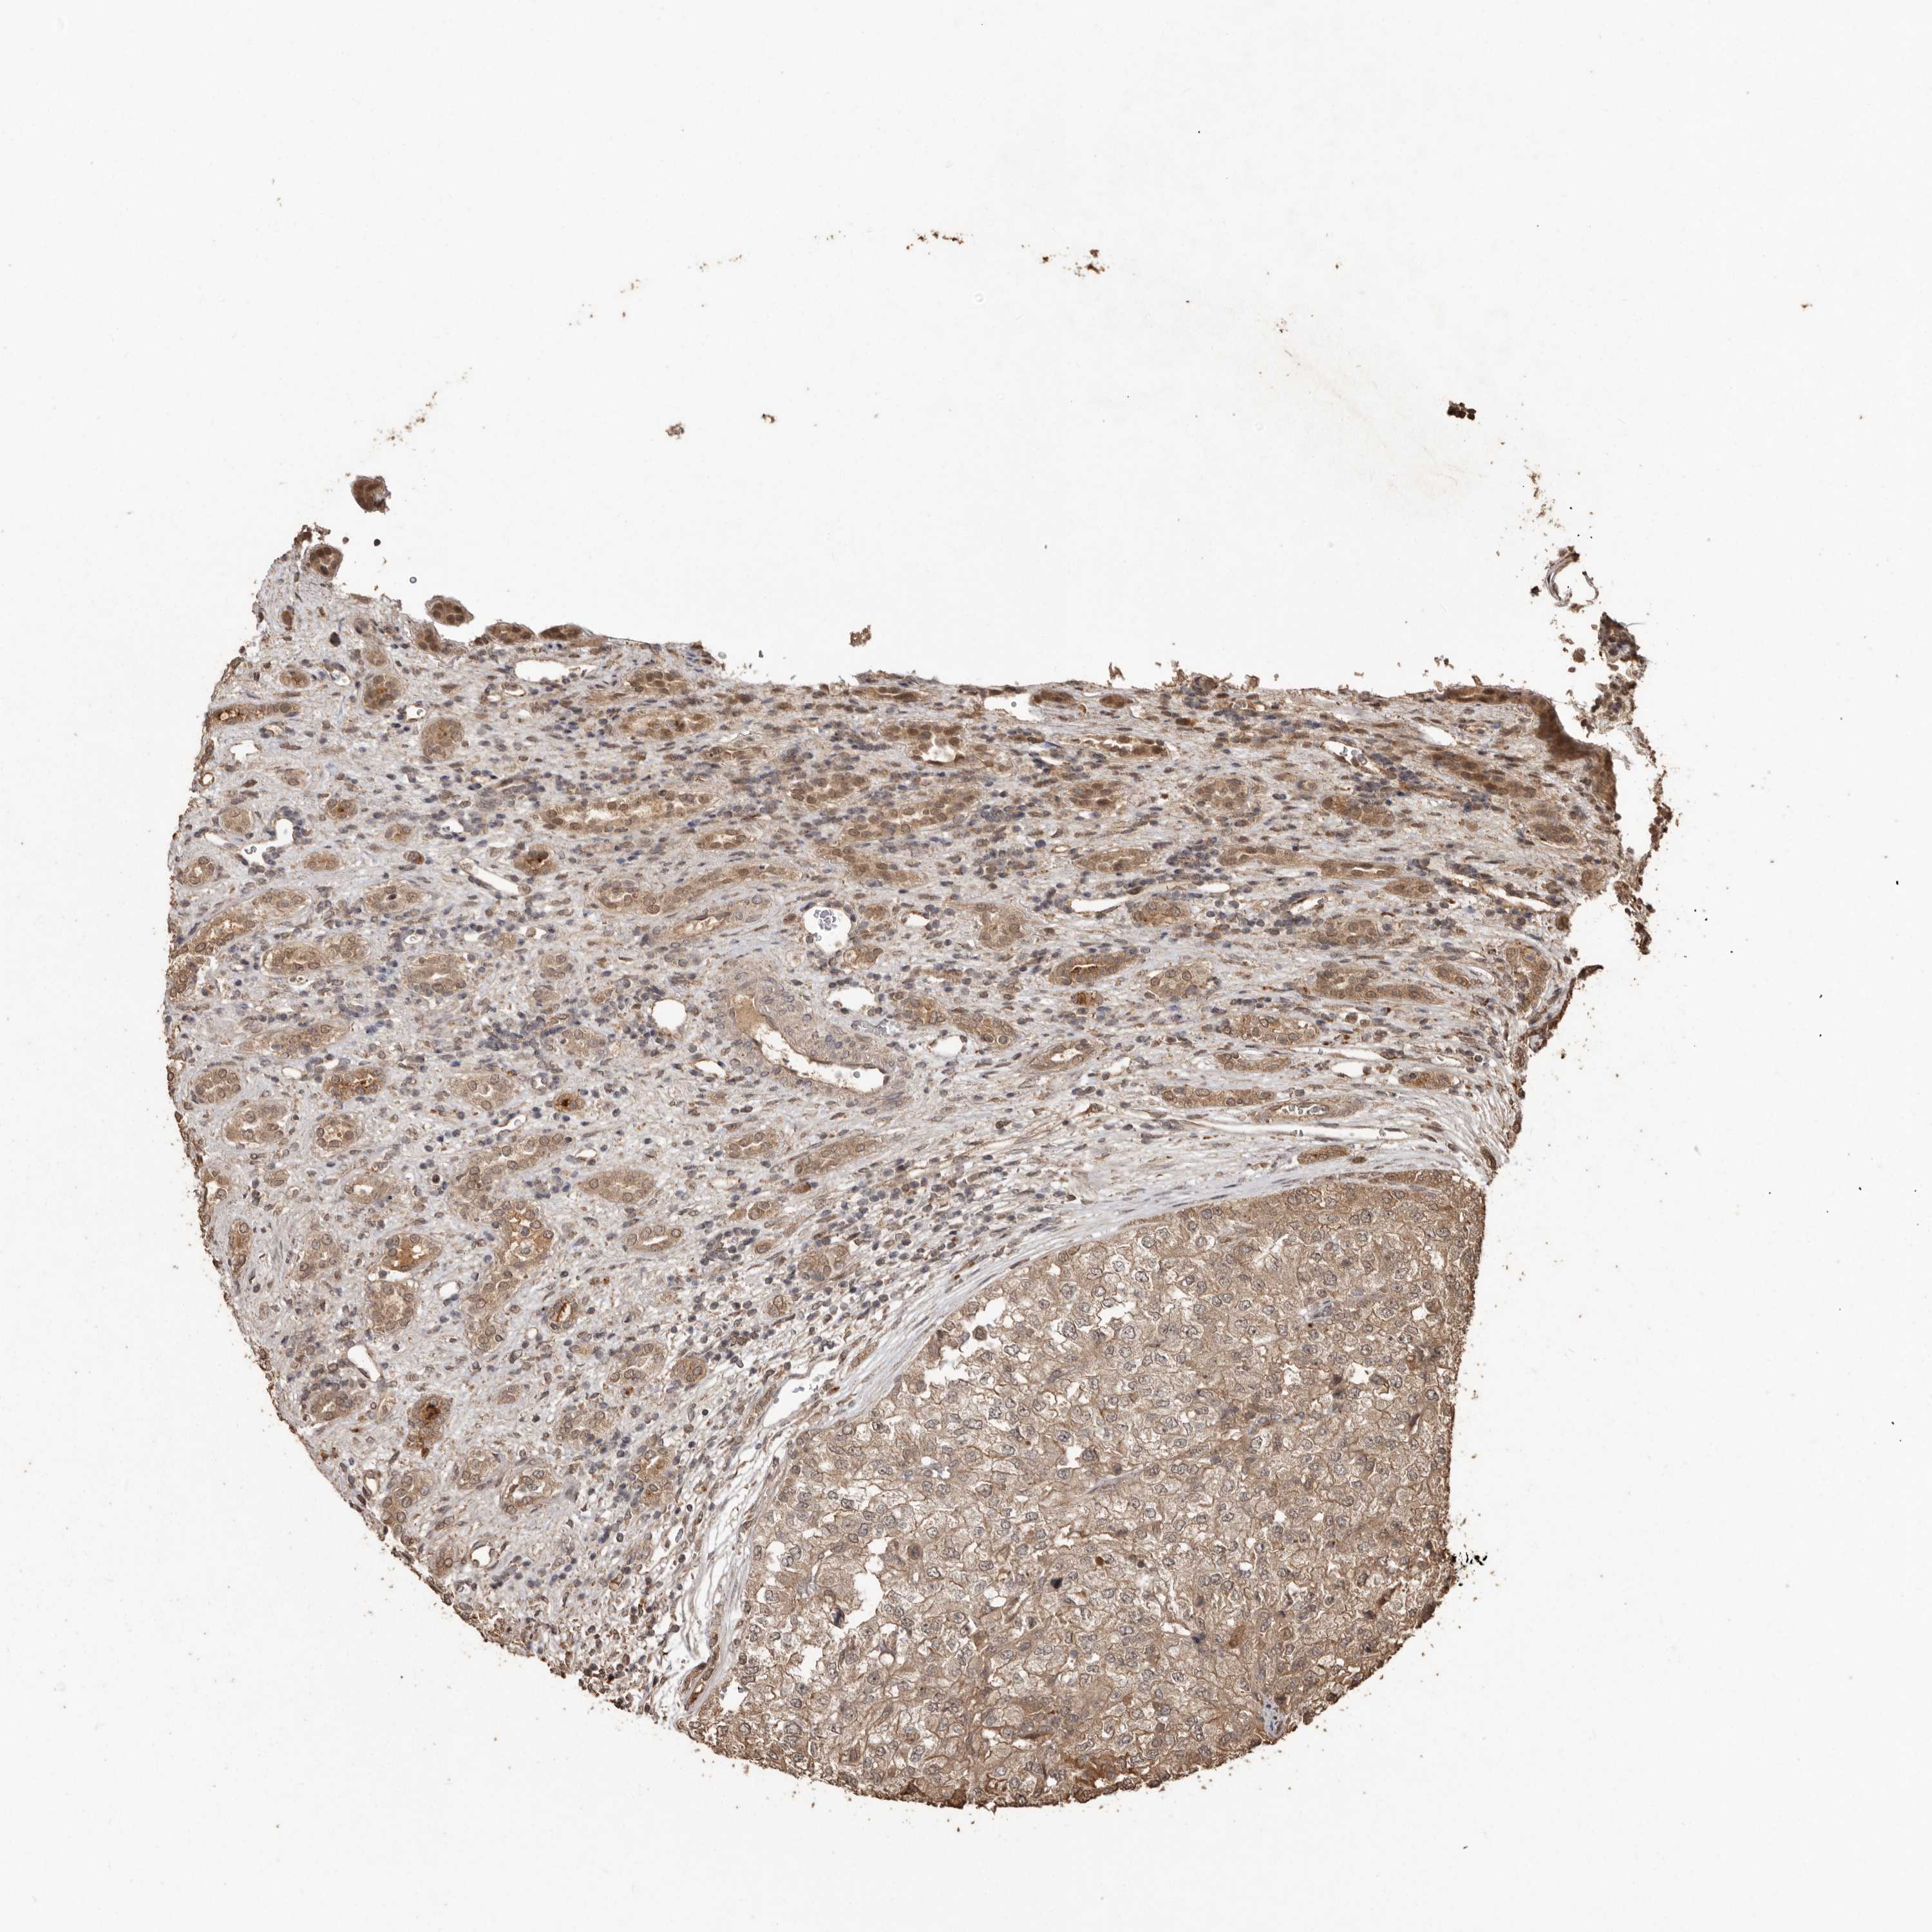

KIDNEY RENAL PAPILLARY CELL CARCINOMA (TCGA) - Interactive survival scatter ploti

The Survival Scatter plot shows the clinical status (i.e. dead or alive) for all individuals in the patient cohort, based on the same data that underlies the corresponding Kaplan-Meier plots. Patients that are alive at last time for follow-up are shown in blue and patients who have died during the study are shown in red.

The x-axis shows the expression levels (FPKM) of the investigated gene in the tumor tissue at the time of diagnosis. The y-axis shows the follow-up time after diagnosis (years). Both axes are complimented with kernel density curves demonstrating the data density over the axes. The top density plot shows the expression levels (FPKM) distribution among dead (red) and alive patients (blue). The right density plot shows the data density of the survived years of dead patients with high and low expression levels respectively, stratified using the cutoff indicated by the vertical dashed line through the Survival Scatter plot. This cutoff is automatically defined based on the FPKM cutoff that minimizes the p-score. The cutoff can be changed by dragging the vertical line or by entering a cutoff value in the square labeled "Current cut-off".

Under the Survival Scatter plot the p-score landscape (black curve; left axis) is shown together with dead median separation (red curve; right axis). Dead median separation is the difference in median mRNA expression between patients who have died with high and low expression, respectively. It is calculated as follows: median FPKM expression of dead patients with high expression - median FPKM expression of dead patients with low expression. This is intended to aid the user in visually exploring custom cutoffs and the associated p-scores and dead median separation.

Individual patient data is displayed and can be filtered by clicking on one or more of the category buttons on the top of the page. Categories describing expression level and patient information include: high, low, alive, dead, female, male and tumor stages. The scale of the x-axis can be toggled between linear and log-scale by clicking on the "x log" button. Mouse-over function shows TCGA ID, patient information and mRNA expression (FPKM) for each patient.

& Survival analysisi

Kaplan-Meier plots summarize results from analysis of correlation between mRNA expression level and patient survival. Patients were divided based on level of expression into one of the two groups "low" (under cut off) or "high" (over cut off). X-axis shows time for survival (years) and y-axis shows the probability of survival, where 1.0 corresponds to 100 percent.

NUP43 is not prognostic in Kidney Renal Papillary Cell Carcinoma (TCGA)

Best expression cut offi